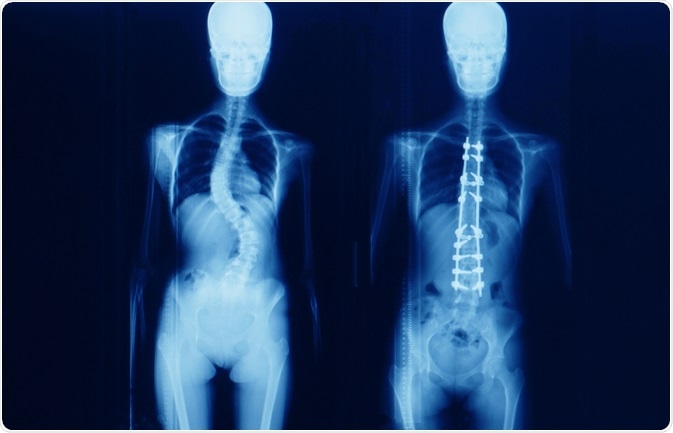

Surgery is usually able to correct the curvature of the spine significantly, but it is rare for the spine to become completely straight as a result of the surgery.

scoliosisImage Credit: Yok_onepiece / Shutterstock.com

Spinal fusion is the most common surgery for patients with scoliosis that have finished growing and involves a graft of bone onto the spinal vertebrae that eventually heal together to form a solid, rigid mass of bone. Although this process may restrict the movement of the spine, it prevents the curvature from becoming worse and may correct severe cases.

There are two main techniques that may be used: anterior fusion provides access to the spine via an incision on the side of the chest wall, and posterior fusion utilizes an incision on the back and metal instruments for the curve correction. The bone graft can be attached to the spine with a combination of metal rods, screws, hooks and wires, which are left in place permanently.